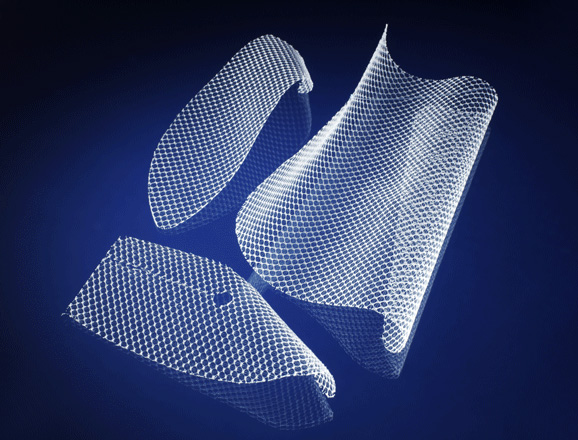

SIATKA PRZEPUKLINOWA

Siatki są z materiału syntetycznego. Co to jest ?

Materiały syntetyczne są wytwarzane od początku do końca przez człowieka – głównie z ropy naftowej i węgla. Z włókien syntetycznych robione są siatki przepuklinowe.

Materiał syntetyczny powstaje w procesie polimeryzacji. Jest to reakcja chemiczna, podczas której związki chemiczne mające małą masę lub mieszaniny kilku takich związków - łączą się ze sobą.